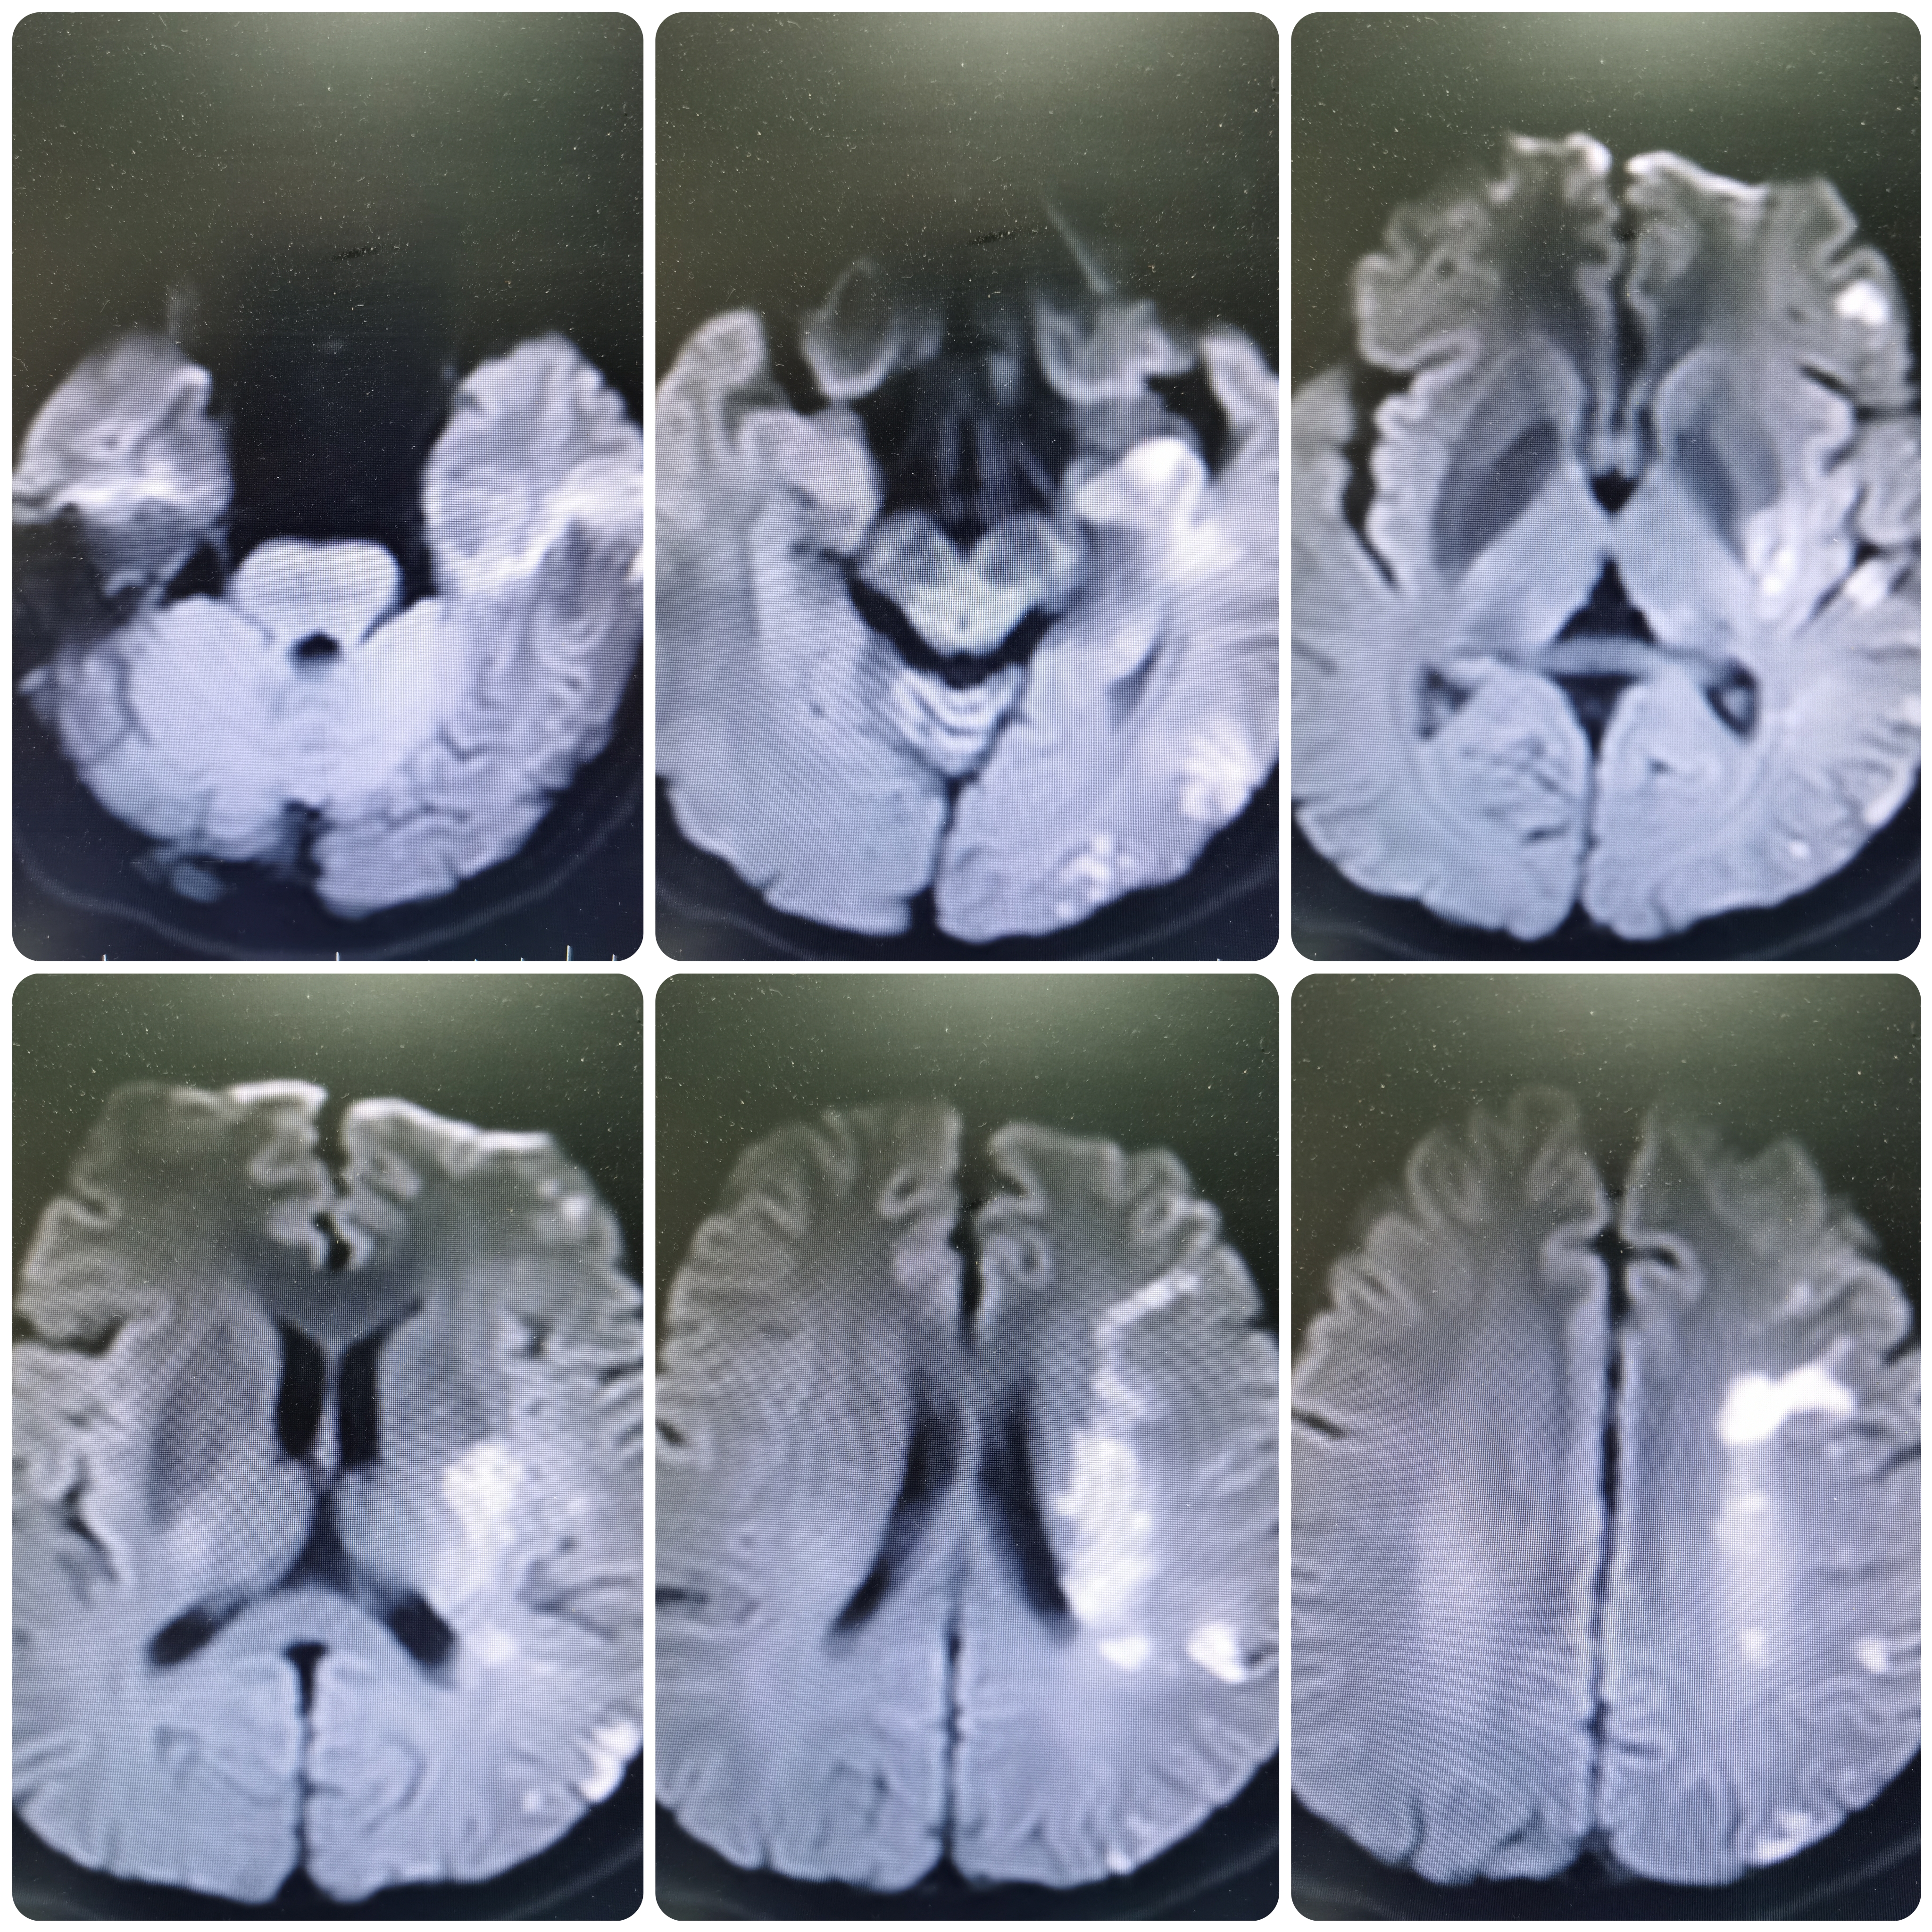

完善核磁DWI示左侧额颞顶枕叶,左侧基底节区 左侧半卵圆中心多发新近脑梗死。

MRA示左侧大脑中动脉闭塞。